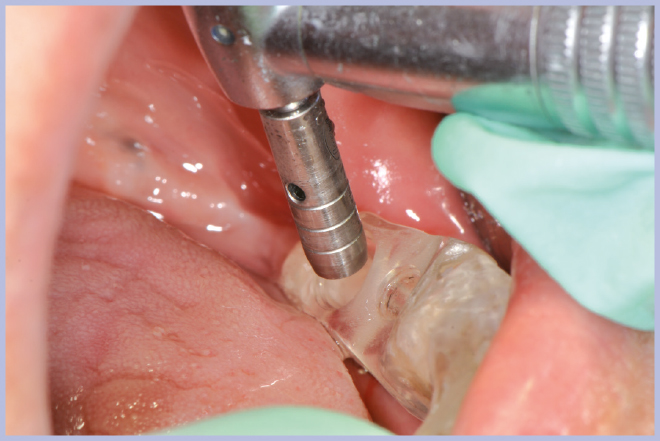

- Figg. 17, 18 – Passaggio dei mucotomi guidati dalla mascherina chirurgica

- Fig. 18